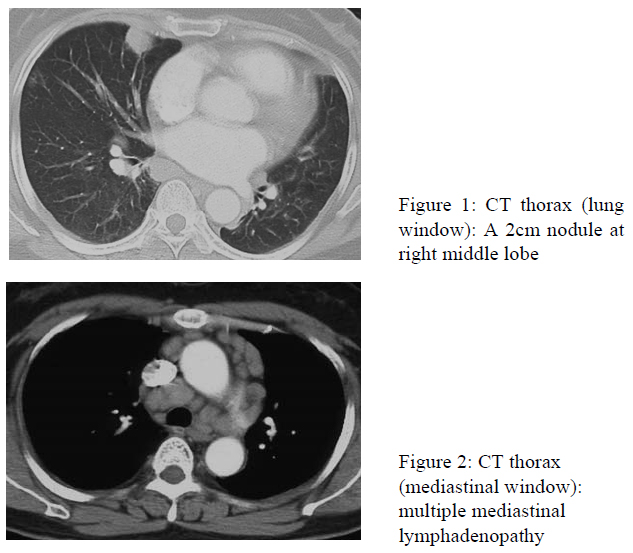

A 56-year-old Chinese lady presented with right loin pain in April 2007. She was assessed by urologist with intravenous urogram showing right ureteric stone and obstruction. She received extracorporeal shock wave lithotripsy. A CT abdomen was performed subsequently to confirm stone clearance which incidentally found a 2cm nodule at right lung.

Her renal function was impaired with creatinine 190 mmol/l and urea 11 umol/l. Adjusted calcium level was 3.04 mmol/l. 24-hour urine for calcium was elevated. Parathyroid hormone was suppressed. Endobronchial ultrasound (EBUS) with transbronchial needle aspiration (TBNA) of the mediastinal lymph nodes yielded non-caseating granulomatous inflammation. The differential diagnoses included tuberculosis, malignancy with lymph node metastases and sarcoidosis. A conventional bronchoscopy with transbronchial biopsy targeted at the lung nodule showed non-specific changes. Bronchoalveolar lavage at right middle lobe was negative for fungal culture, polymerace chain reaction for tuberculosis and acid fast bacilli (AFB) culture. Fine needle aspiration of the lung nodule under CT guidance yielded atypical cells. She then proceeded to open biopsy of right middle lobe nodule and mediatinal lymph node sampling via video-assisted thoracosopic surgery. The histology revealed non-caseating granuloma and stains for AFB and fungus were negative. The ultimate diagnosis was sarcoidosis. She was treated with prednisolone with good response.